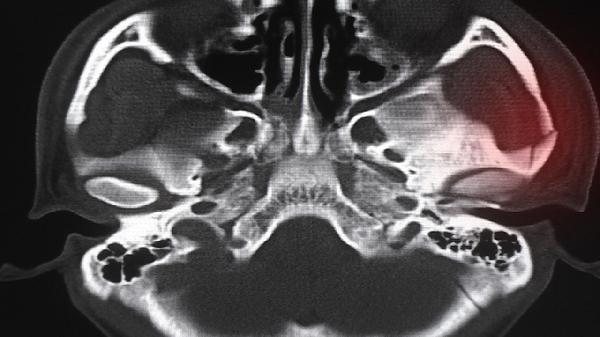

建议定期进行胸廓对称性自检,站立位观察锁骨、乳头连线是否水平。青少年生长发育期应保证每日600国际单位维生素D摄入,避免单侧负重书包。出现呼吸困难、心悸等伴随症状时需及时就诊胸外科,通过CT三维重建评估骨骼畸形程度。睡眠时保持仰卧位有助于减轻胸廓不对称进展。